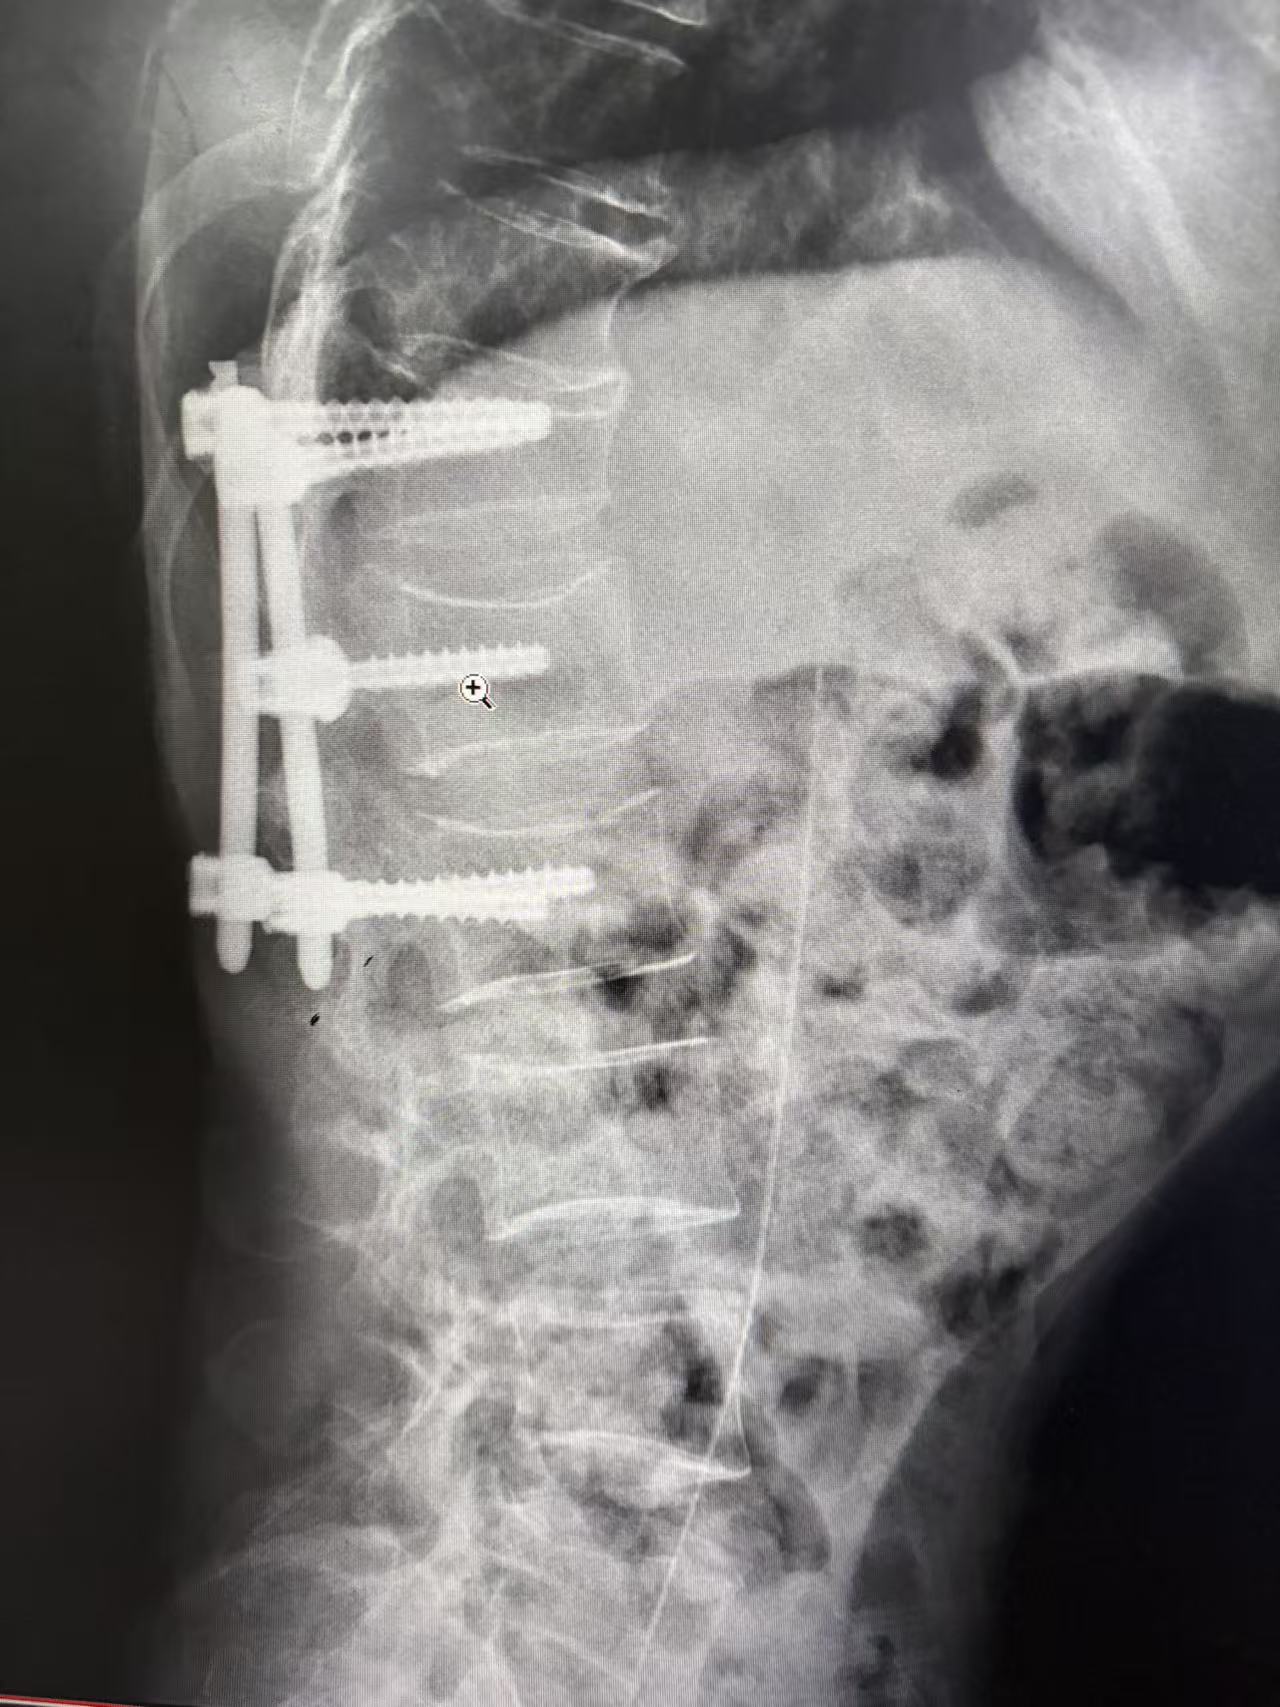

△置管术后定位的X线

面对这一棘手难题,南华医院肿瘤一区静脉治疗护理团队迎难而上,在科室主任唐三元教授及护士长欧娜的带领下,经过缜密的术前讨论和评估,果断决定为患者实施“经下腔静脉PICC置管术”。术中,团队凭借丰富的经验和娴熟的配合,在超声引导下精准穿刺患者的股静脉,并结合如同“GPS导航”一般的心电定位技术,清晰地指引着导管尖端准确到达理想位置,整个过程顺利,患者无特殊不适。这条经由股静脉建立的“生命通道”,成功绕开了被肿瘤压迫的“禁区”,为后续的化疗、营养支持等生命治疗提供了坚实保障。